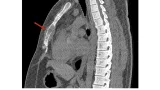

20歳代の殿部痛の患者さんは, 仙骨を圧すと痛みがあったので, 骨盤のCTを撮像しました. 仙骨の5番目の部分(第5仙椎)が骨折して, 折れ曲がっていました. 入院は希望されず, 何とか歩けたので, 鎮痛薬を処方して, 整形外科クリニックに紹介しました.

骨折した部分でズレています.

引用元:White JH. Imaging of sacral fractures. Clin Radiol. 2003. 58.